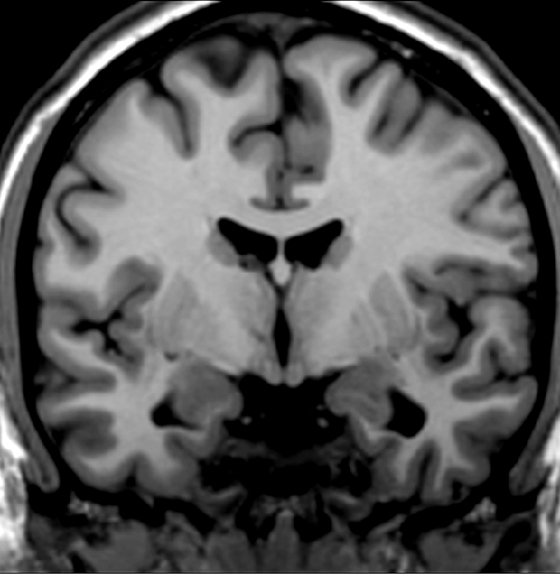

Click on the landmark that delineates thalamus from hypothalamus.